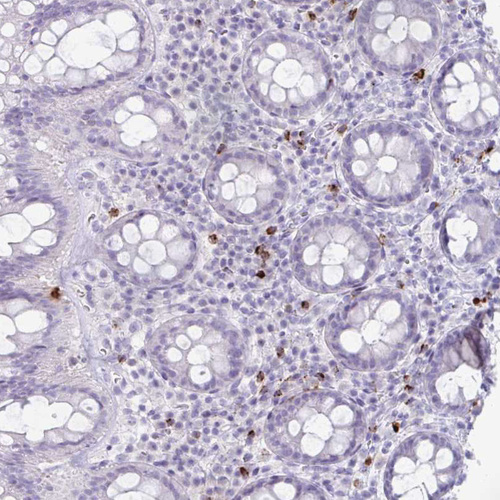

Immunohistochemical staining of human skeletal muscle shows no positivity in myocytes as expected.